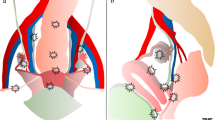

Posterior Compartment

Recently, the ultrasound features of the deep infiltrating endometriosis nodules have been systematically defined by the International Deep Endometriosis Analysis group [34]. The most common sites of the posterior compartment are posterior vaginal fornix/rectovaginal septum, uterosacral ligaments, anterior rectum/anterior rectosigmoid junction, and sigmoid colon [10] (Fig. 4).

Deep endometriosis on sonography is subtle and presents as hypoechoic nodular or infiltrating regions. Occasionally, the infiltrative regions of DIE may have internal hyperechoic foci or complex internal cysts [50]. The differential diagnosis for DIE includes peritoneal implants; in these cases, to help differential diagnosis, an additional evaluation with MR is recommended [18]. Three-dimensional (3D) TVS has been also proposed in the evaluation of posterior locations of DIE without intestinal involvement, improving the diagnostic accuracy of 2D ultrasonography [51].

Rectovaginal Septum

Involvement of the rectovaginal septum should be suspected when an endometriotic nodule, which appears as hypoechoic solid nodule with smooth or irregular contours, that replaces the normal hyperechoic aspect of this layer between the vagina and the rectum, seen in the rectovaginal space below the horizontal plane passing through the lower border of the posterior lip of the cervix (under the peritoneum) [34].

Isolated rectovaginal septum nodule is rare, and it is usually an extension of posterior vaginal wall, anterior rectal wall, or both posterior vaginal wall and anterior rectal wall involvement. Hourglass-shaped or diabolo-like nodules can occur when endometriosis lesions from the posterior vaginal fornix extend to the anterior rectal wall [54].

DIE of the RVS may extend into the rectum and/or in the posterior vaginal fornix [22].

Major discrepancies exist between the pooled sensitivities and specificities provided by meta-analyses reporting values from 49% to 88% and 98% to 100%, respectively [34].

Bowel

The endometriosis affecting the bowel can appear as a thickening of the muscularis propria or as a hypoechoic nodule penetrating the intestinal wall with blurred margins, with or without hypoechoic or hyperechoic foci, usually associated with retraction and adhesion (the so-called Indian headdress sign), and few vessels at power Doppler evaluation [57].

The rectum and the rectosigmoid segment is the most frequent site of bowel involvement accounting for 70–88% of cases of bowel involvement with endometriosis, followed by the sigmoid colon, rectum, ileum, appendix, and cecum [10]. Intestinal nodules located below the peritoneum of the POD (or the level of the insertion of the USLs on the cervix in case the cul-de-sac is obliterated) are considered low rectal lesions, while the ones above this level are considered upper rectal or the rectosigmoid junction lesions. This virtual line should delineate the plane under the peritoneum of the POD and correspond laterally to the parametria and medially to the RVS. The lowest limit of the nodule on the bowel wall should be determined, because the lower rectal lesions are more difficult to remove surgically by shaving or segmental resection and have higher complication rate [22].

Endometriotic nodules of the rectum can be evaluated if necessary also by transrectal examination as well with the same transvaginal convex probe. This has the advantage of visualizing better the vagina, the rectovaginal septum (RVS), and the low rectal walls. Moreover, during the transrectal or transvaginal examination, a fluid contrast medium can be inserted in the vagina to visualize better the RVS (sonovaginography) [55]. It has been reported that adding water contrast in the rectum during transvaginal ultrasonography (RWC-TVS) improves the diagnosis of rectal infiltration in women with rectovaginal endometriosis. RWC-TVS is performed by injecting saline solution into the rectal lumen under ultrasonographic control through a catheter [58].

During the evaluation of posterior compartment, a negative “sliding sign” between the rectosigmoid and uterus could indicate an obliteration of the pouch of Douglas (POD), frequently associated with severe DE. Using this new technique, Reid et al. found sensitivity, specificity of 83.3%, 97.1% [59].